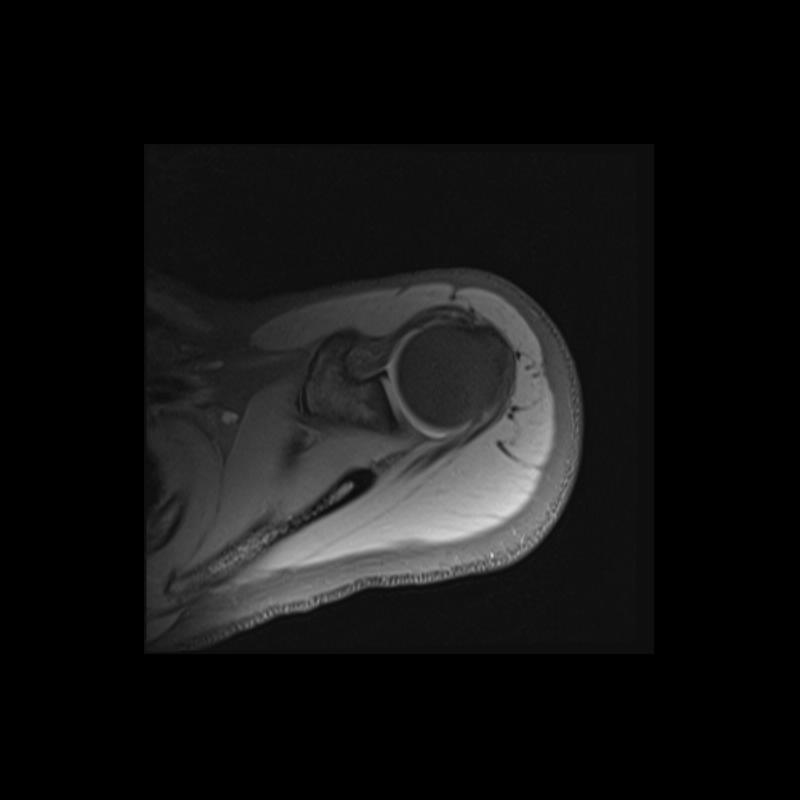

Shoulder MRI Anatomy